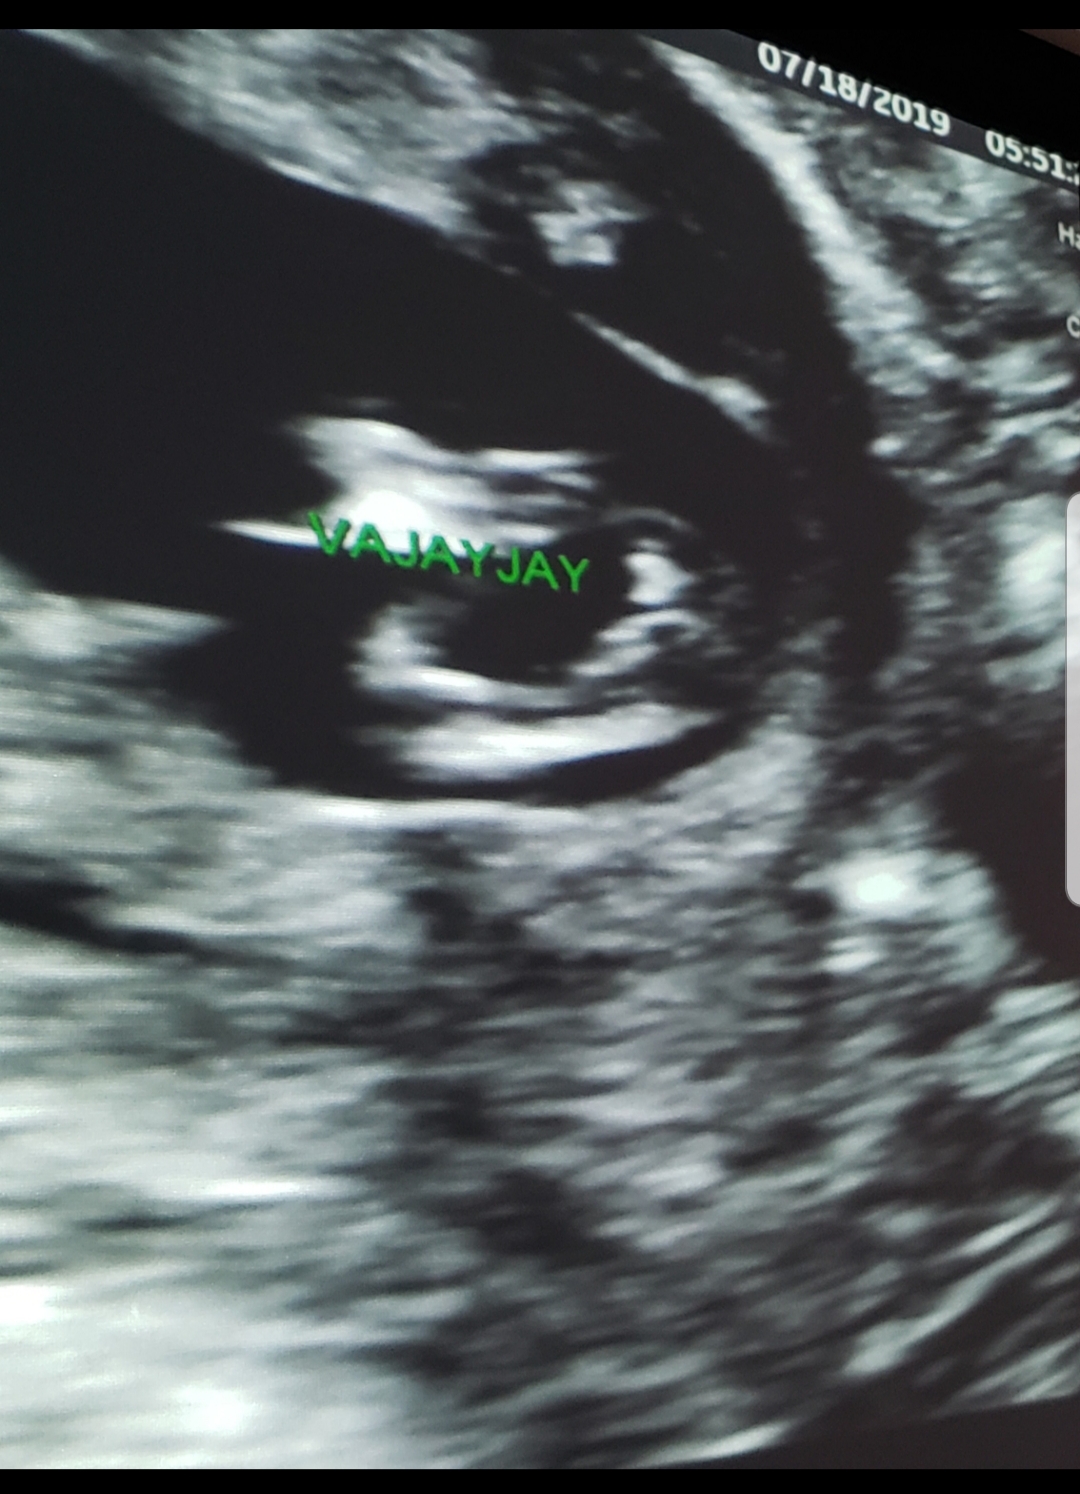

Ok, so humor me.. I had myself convinced that this was going to be boy number 4 (I swayed but was feeling really pessimistic and felt like I should accept that this is another boy..) I reluctantly went to a "gender reveal" ultrasound so the boys could see the baby and my parents were able to make it.

Long story short the tech spent a good 20-30 minutes verifying and the baby was really cooperating. She seemed convinced that we're having a girl. I was only 14 weeks and it does look very different from my boys.. I'm still in shock and disbelief. I want to get a second opinion before I start letting myself get excited about this!

Attachment 41809

Attachment 41807

"vajayjay!" hahaha ive never seen that written on a scan pic before!! 14 weeks is early but that does look really girly, id be pretty confident especially as the tech took a really good look and got clear shots. Congratulations!! :)

Honestly, I don't know any sonographers that would confidently tell someone gender at 14 weeks. We just don't do it. (I am a sonographer.) It does look girlie but I do also question the quality of a sonographer who would tell someone definitively that early, that's just me though. And there's no way our doctors would call it. I would tell someone it looks girlie to me but it's too early to say for sure. Good luck! I do hope it's your girl!

it's def. girly but I would not paint the nursery just yet. :)

I agree with the other comments, looks girly but 14 weeks is really early. One week later would have been much more reliable.